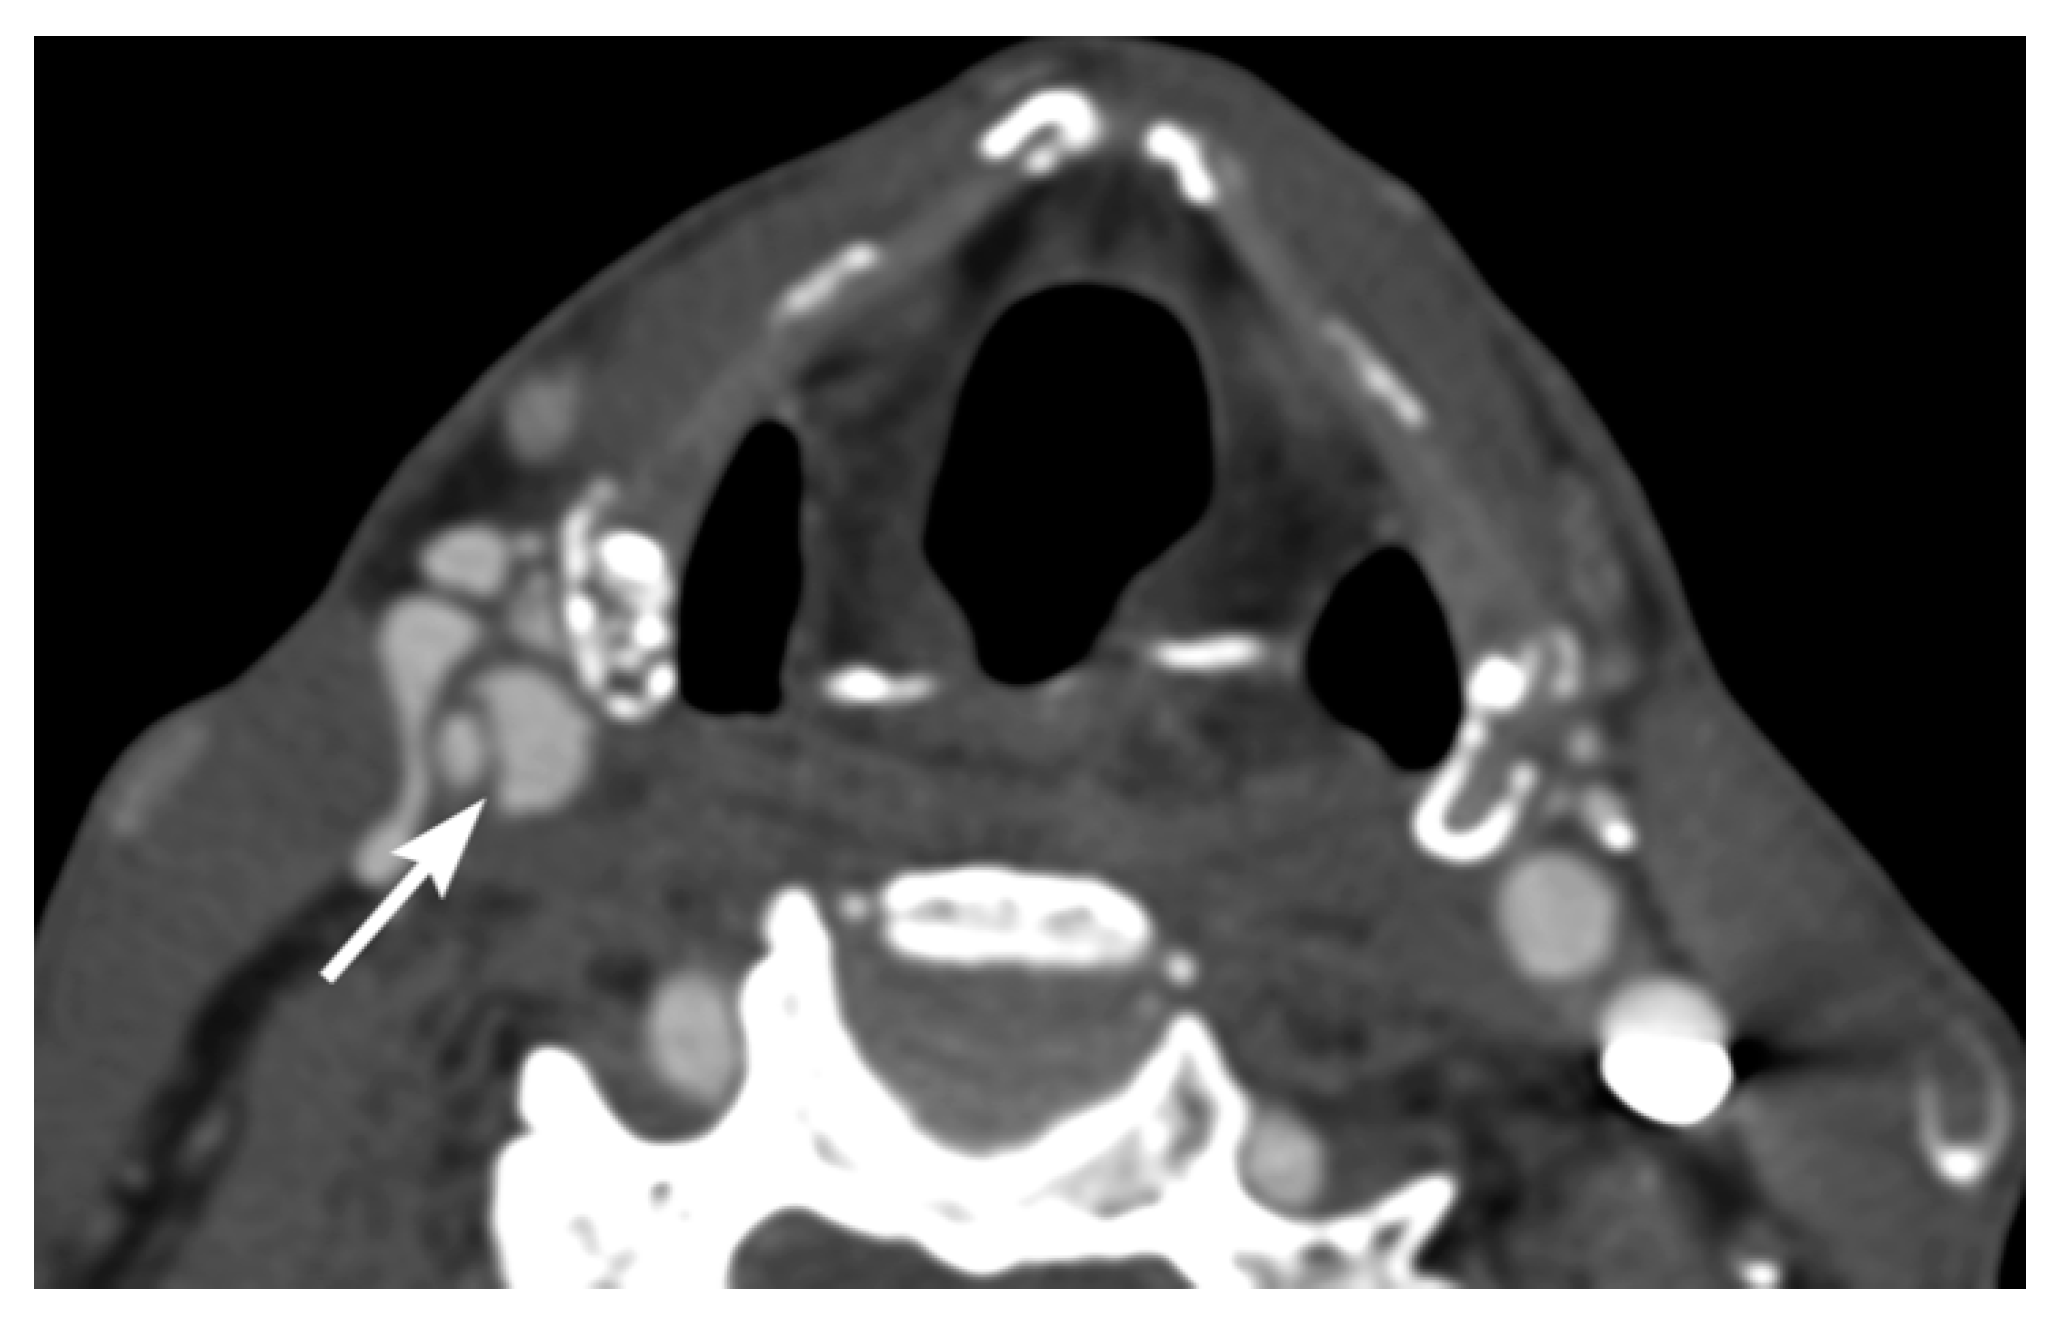

3. Imaging Findings of Arterial Injury